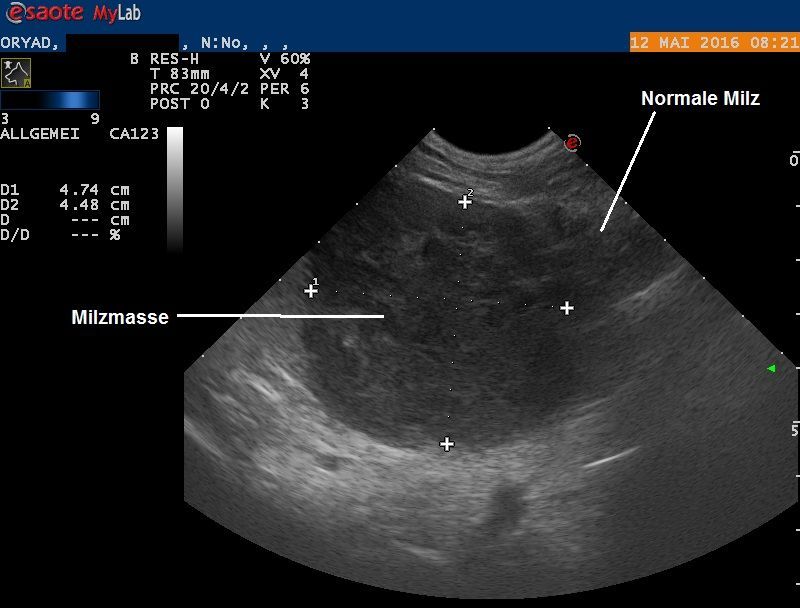

Obwohl nun bekannt ist, dass sich im Bauch des Hundes ein Knoten verbirgt und dieser zielgerichtet abgetastet werden kann, erweist sich die Masse als nicht ertastbar. Im Ultraschall findet sich dann aber ein knapp 5 cm messender, kugeliger Knoten innerhalb der Milz. Der Knoten zeigt eine heterogene (uneinheitliche) Echotextur und enthält auch kleine Hohlräume, welche mit Flüssigkeit gefüllt scheinen. In der Bauchhöhle findet sich aber keine Flüssigkeit, die restlichen Bauchorgane erscheinen unauffällig, und auch ein kurzer Ultraschall des Herzens verläuft unauffällig.

Da davon ausgegangen werden muss, dass der Milzknoten für den verschlechterten Allgemeinzustand von Oryad verantwortlich ist, wird der Entscheid zur Entfernung der Milz gefasst. Eine vorgängige Gewebeprobe mittels Feinnadelaspiration wird nicht durchgeführt, da bei zwei der möglichen Geschwulsttypen (Hämangiosarkom sowie Bluterguss, siehe Fall 19 ) eine Gewebediagnose sehr schwierig ist und mit einem starken Blutungsrisiko verbunden ist.